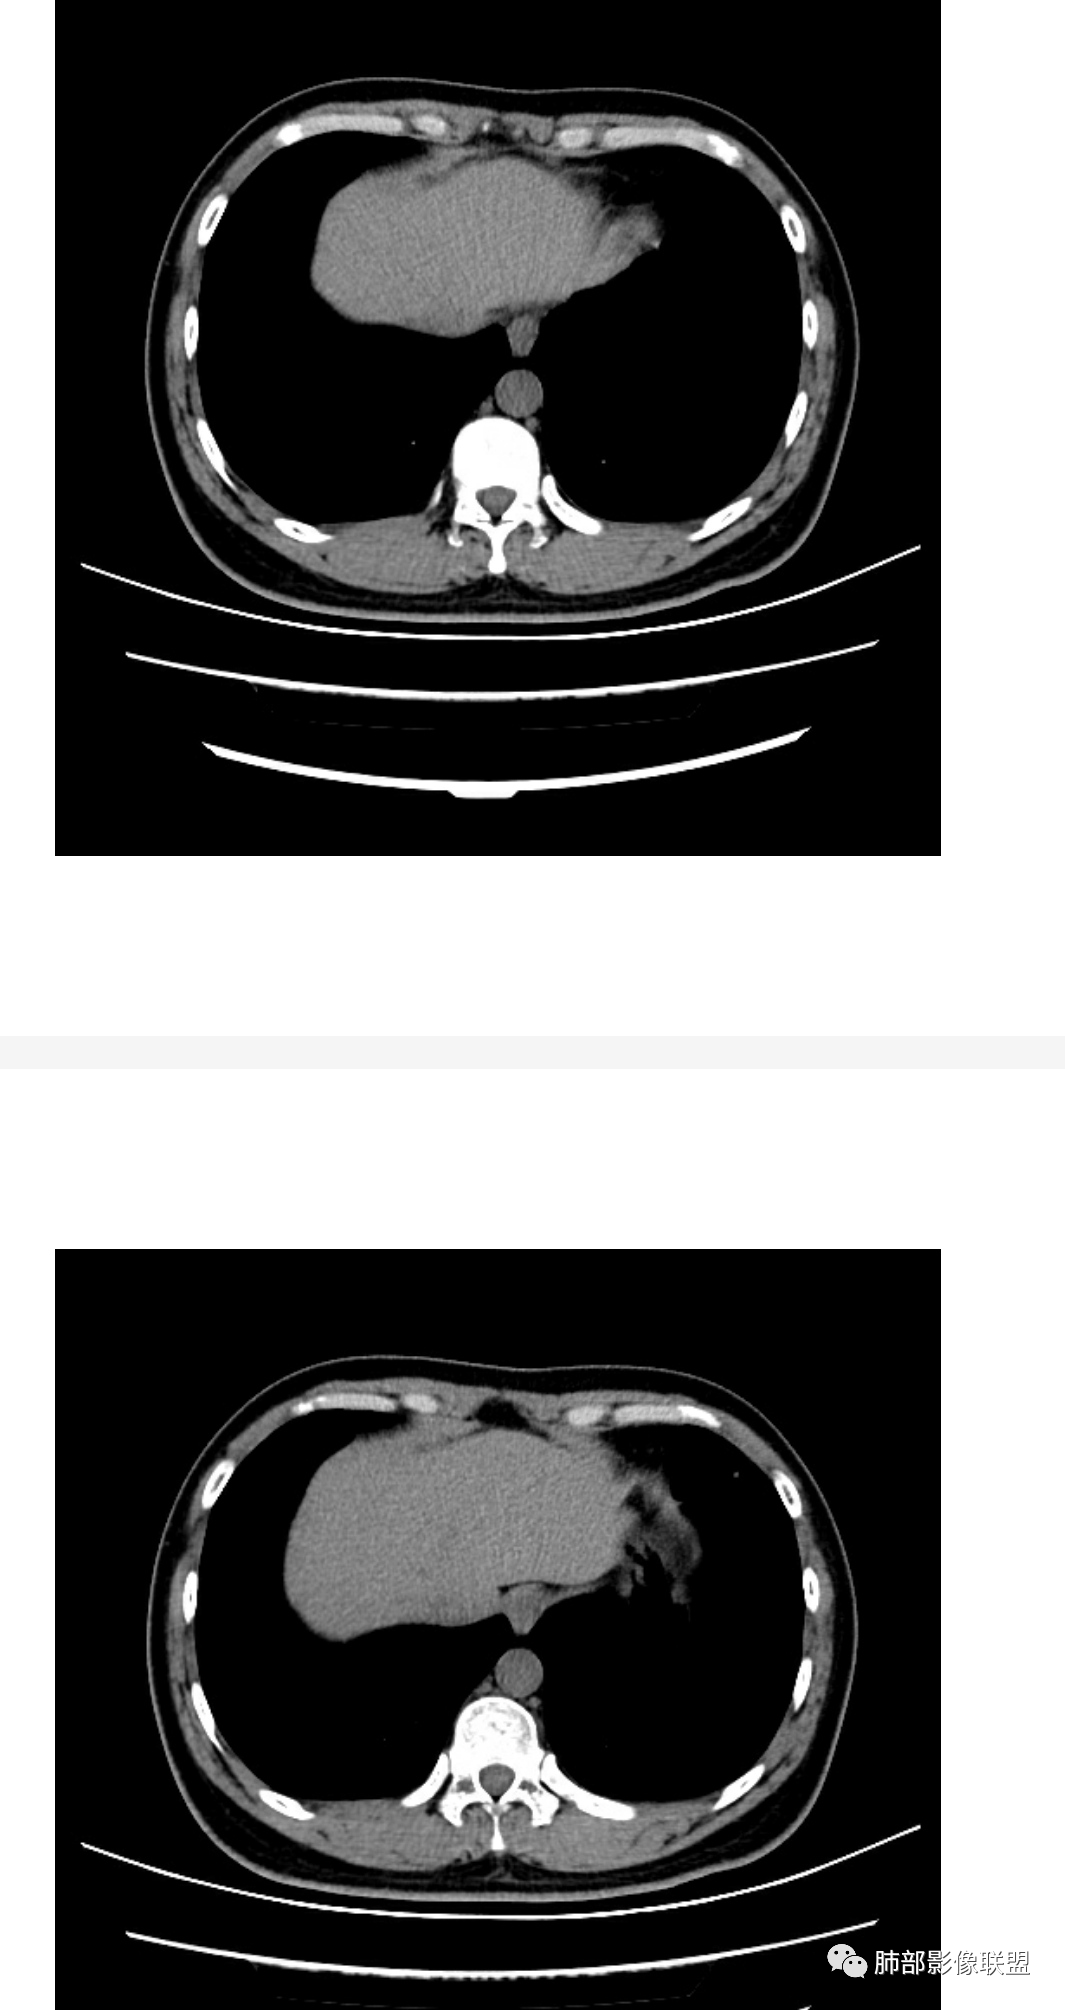

这样的Cd4如此低,病情那么久了,隐球菌的话,脑子应该出问题了,但是患者没有中枢神经系统受损表现,马尼入血后可以出现呼吸困难。诊断真菌性机会性感染没问题,还是马尼>隐球菌。

青年男性,HIV阳性,白细胞及淋巴细胞显著降低,CRP增高,胸闷气喘一周,影像为双肺胸膜下平行于胸膜分布的多发大小不等结节伴晕,单从影像上看,隐球是要首先考虑,但是不好解释临床症状。需要鉴别:1、曲霉所致IPA,临床有粒缺基础,胸闷一周要考虑,但影像不是典型的血道或气道分布又存疑,2、马尼,CD4低,HIV基础,要考虑,但是否有旅广史?另外纵隔淋巴结无肿大,肝脾不肿大,可能稍小。3、PCP,HIV基础,CD4低,胸闷气喘要考虑,影像分布不典型。4、腺病毒或EB病毒感染,HIV基础,影像改变要考虑,但是发病无发热,存疑。5、结核,临床与影像均不典型。可能小。综上,隐球>曲霉>PCP>马尼>病毒感染。下一步,查隐球荚膜抗原,NGS找病原体。

老师们最多鉴别的是马尼。马尼主要还是纵隔淋巴结,腹膜后多发淋巴结,肝脾大。我收集的病例还是以淋巴结肿大显著,有的时候双肺可以干净的很,可能就在一个角落里孤立的一个空洞

肺隐球菌多分布在肺野外带或胸膜下区域,下叶多见,可能余隐球菌更容易在胸膜下肺泡中定植或蔓延有关;显示腺泡结节,然后取决于宿主免疫,可以入血,然后血播

如果是血播是随机分布,他这个是胸膜下

不是血道,就是直接吸入到远端肺泡

今天这个没有血播依据